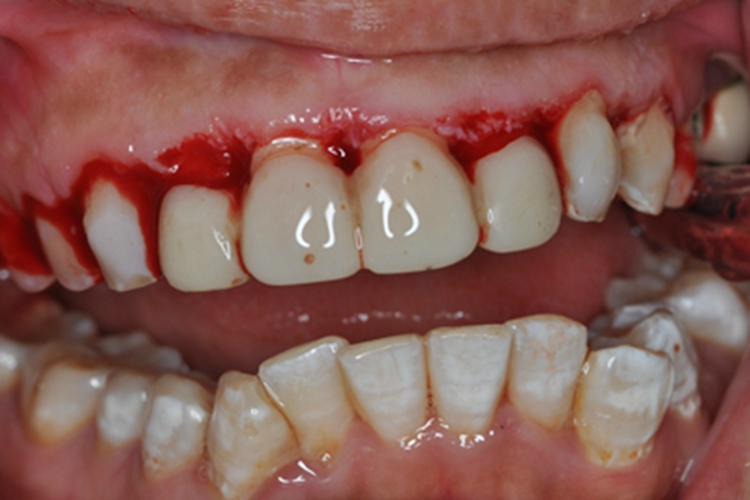

急性坏死性龈口炎可出现牙龈出血的情况,早期牙龈边缘及龈乳头红肿,以后迅速坏死,使龈缘变平,龈乳头呈“刀削样”缺损,表面覆盖灰褐色污秽假膜,患处牙龈易出血,疼痛明显,口内有特殊的坏死性口臭。